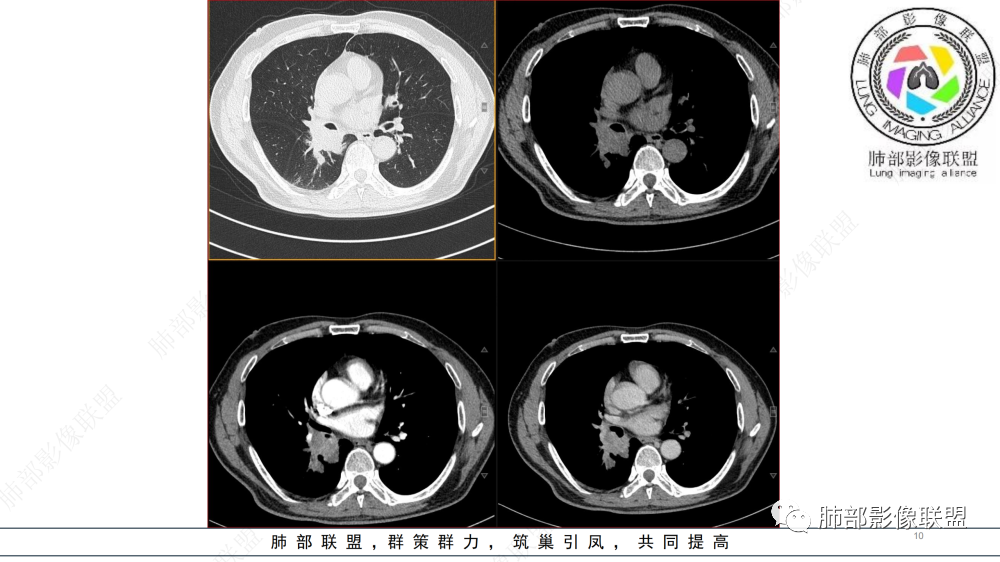

晨读 右肺中间段支气管至下叶支气管部分狭窄及堵塞,管壁偏侧增厚腔内外侵犯,软组织肿块形成,远侧肺内阻塞性炎症。考虑恶性病变,鳞癌,类癌可能

中年男性,咳嗽咳痰半年,有痰中带血,肿瘤标志物角蛋白稍高,右肺下叶支气管腔内肿块,支气管截断,有强化,考虑肺癌,鳞癌可能,鉴别类癌,粘液表皮癌等。

中年男性,痰中带血,病史半年,一直没有发热,感染指标不高,胸部CT右侧肺门不规则肿块影,边缘清楚,棘状突起,浅分叶,血管集支束,空泡征,不均匀强化,右肺斜裂结节状增厚,右侧中间支气管外压改变,右肺下叶背段支气管截断,无明显淋巴结肿大,恶性是没有问题,至于类型病灶大无坏死空洞,鳞癌靠后,无明显淋巴结肿大,小细胞靠后,所以腺癌首选。

晨读 右肺中间段支气管至下叶支气管狹窄,腔内见软组织肿块,腔内外侵犯,右下肺门软组织肿块形成,不均匀强化,冠状位病变纵径大于横径,远侧肺内阻塞性炎症。定性恶性,考虑腺样囊腺癌或鳞癌

晨读:男,57岁,咳嗽咳痰半年,右肺下叶支气管腔内肿块影,管壁增厚,管腔狭窄,增强扫描呈不均匀性强化,考虑恶性病变,鳞癌可能。

晨读病例,中年男性,咳嗽咳痰半年,有痰中带血,影像表现右肺下叶支气管腔内外占位,形态欠规则,有冰山征表现,支气管截断,有强化,考虑恶性病变,类癌或鳞癌可能,鉴别腺癌、粘液表皮癌等。

右肺下叶肺门区肿块,向中间段支气管突出,下叶支气管阻塞狭窄,腔内外侵犯,不均匀强化,内可见低密度,冠状位病变沿支气管走行生长,远侧肺内阻塞性炎症,考虑鳞癌,鉴别类癌

中老年男性,右肺下叶背段支气管内新生物,近端可见息肉样突起,远端沿分支支气管生长堵塞,肺门口病灶增强后明显强化,峰值达140hu,远端部分强化不明显考虑粘液栓,考虑典型类癌,鉴别鳞癌。

右肺叶中间段支气管见软组织影不完全阻塞及管腔变窄,向管腔外突破,向下叶背段浸润性生长,见指套及息肉样特点,不均匀明显强化,右肺下叶背段少许阻塞性炎症,肯定恶性肿瘤,小细胞Ca首先,支气管疾病谱恶性肿瘤:类癌,鳞癌,囊腺癌,粘液表皮样癌,与鳞癌,囊腺癌鉴别,支气管镜取材活检可以明确诊断。

晨读:男,57,咳嗽半年,痰中带血3天。胸部CT:右中间段支气管到下叶支气管堵塞性狭窄,管腔内见软组织肿块,壁内外侵犯,长轴沿气道延展,下叶基底多段累及,病变纵径大于横径,远侧可见索条、阻塞性炎症。考虑恶性,腺样囊腺癌?鳞?鉴别N内分泌类、炎性肉芽肿等